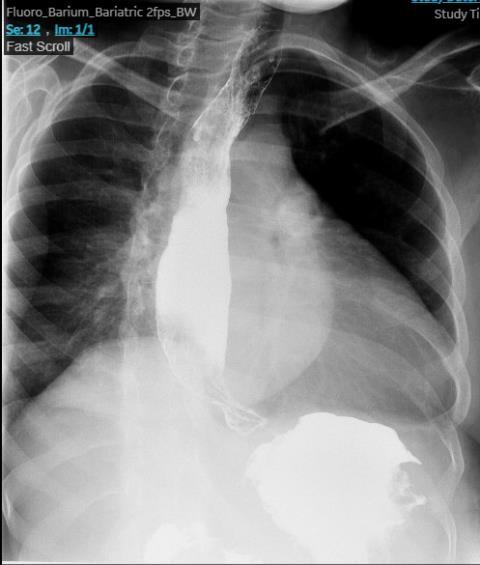

BURKITT LYMPHOMA INDUCED PSEUDOACHALASIA WITH DRAMATIC SYMPTOMATIC IMPROVEMENT POST-CHEMOTHERAPY

68

Marni H. Wilkoff1 , Emily S. Seltzer1 , Allison E. Wang1,2 , Bruno Almeida Costa1 , Bruce Gelman1

1Mount Sinai Morningside-West Hospitals, Icahn School of Medicine at Mount Sinai, New York, NY, United States;

2Mount Sinai Beth Israel Hospital, Icahn School of Medicine at Mount Sinai, New York, NY, United States 69